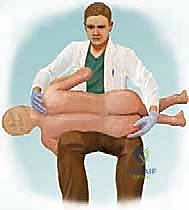

In the operating theater, patient positioning is a meticulous, time-consuming process that demands the surgeon's direct supervision. The patient is typically placed prone on a specialized four-poster frame or a Jackson spinal table. The primary goal is to allow the abdomen to hang completely free. Any abdominal compression will translate to increased intra-abdominal pressure, engorgement of the epidural venous plexus (Batson's plexus), and subsequent torrential intraoperative bleeding. Meticulous padding of all bony prominences, particularly the face, axillae, and peroneal nerves, is non-negotiable to prevent devastating positioning palsies.